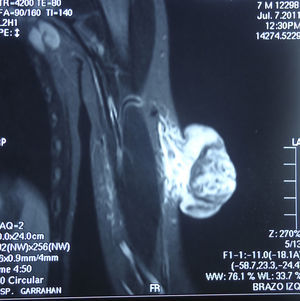

En la exploración se observó en el brazo izquierdo una lesión tumoral exofítica y pediculada, de consistencia pétrea, de 8cm de diámetro, con pérdida de la piel suprayacente, quedando expuesta la superficie erosionada con un lecho sangrante de aspecto crateriforme (fig. 1). Se realizó una resonancia magnética nuclear (RMN) y una angiorresonancia, visualizándose una formación exofítica con un nódulo heterogéneo y un halo hipointenso dentro de un tejido hiperintenso, con gran cantidad de vasos tortuosos en su pedículo (fig. 2). Se realizó exéresis quirúrgica reconstruyendo el defecto mediante un colgajo de Dufourmentel. El estudio histopatológico demostró la presencia de «lóbulos de células basaloides con maduración hacia la luz y formación de células con citoplasma abundante eosinófilo y láminas de detritus queratósicos eosinofílicos y queratinización de tipo pilar. Rodeando los lóbulos el estroma era fibroso con infiltrado inflamatorio mononuclear e histiocitario, con formación de células gigantes multinucleadas tipo cuerpo extraño. Se observaban numerosos focos de calcificación distrófica. Dichos hallazgos eran compatibles con el diagnóstico de pilomatrixoma gigante con reacción gigantocelular de tipo cuerpo extraño» (fig. 3). El paciente evolucionó favorablemente sin recidivas posteriores tras un año de seguimiento.

Como exámenes complementarios la ecografía evidencia una lesión ecogénica con sombra acústica posterior. En este caso la RMN evaluó la extensión y evidenció una formación exofítica con hipervascularización, ya reportada en otro caso de pilomatrixoma gigante9.